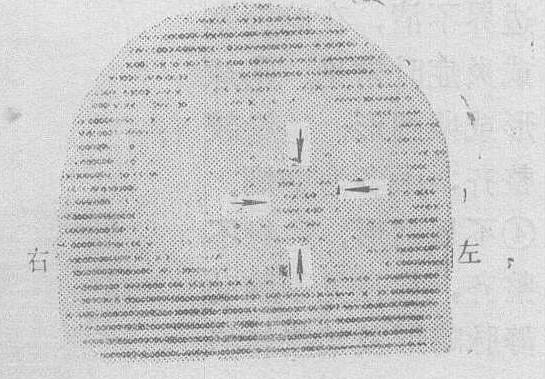

❻99mTc从放射性核素99Mo“发生器”中获得,可以口服,适合体外扫描,图像清晰 (图4ab),虽剂量较大,对全身和局部照射量低,因此已被广泛采用。其缺点为不能较长时间贮存,每周必须更换“发生器”。常用标记化合物有: 99mTc (过锝酸盐),99mTc磷酸盐以及99mTc血清白蛋白等。

图4a 前后位,左额星形细胞瘤99mTc 15mCi

图4b 左侧位,同上